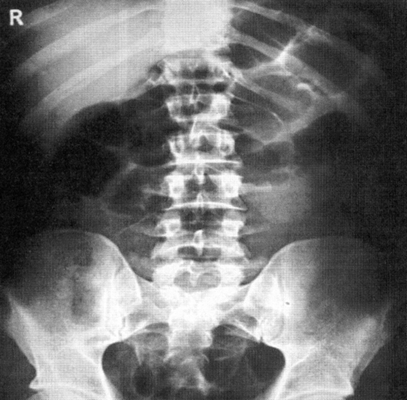

Назначение снимка—получение общего представления о положении, форме и размерах органов живота, а также выявление свободного газа в брюшной полости, уровней жидкости в раздутых газом петлях кишок (чаши Клойбера), обызвествлений и конкрементов в проекции желчного пузыря и почек, металлических инородных тел в брюшной полости или брюшной стенке. Кроме того, в отдельных случаях к обзорной рентгенографии живота прибегают в акушерской практике с целью определения числа,

Укладка больного для выполнения снимке. Снимок выполняют у вертикальной стойки. Больной прижимается к кассете брюшной стенкой.

Голова расположена прямо, руки опущены. Фокусное расстояние — 100—120 см. Размеры кассеты — 30X40 или 35X35 см.

Верхний край ее располагается на уровне IX грудного позвонка. Центральный пучок рентгеновского излучения направляют на линию остистых отростков, на 1—2 см выше гребней подвздошных костей, в центр кассеты. Съемку осуществляют при задержанном дыхании, после форсированного выдоха и втягивания живота (рис. 537).

Информативность снимка. На обзорной рентгенограмме (электро-рентгенограмме) живота отображаются очертания печени, почек, больших поясничных мышц, желудка и кишечника (при наличии в них газа), а также диафрагма, вход в малый таз и боковые каналы брюшной полости (рис. 538).

На обзорных снимках живота, выполненных в положении больного стоя или сидя, хорошо видны раздутые газом кишечные петли с уровнями жидкости при кишечной непроходимости

На правильно выполненном снимке должны быть хорошо видны очертания паренхиматозных органов живота, диафрагма, нижние ребра, проксимальные отделы подвздошных костей и боковые отделы брюшной полости.

Позвоночник при симметричной укладке и отсутствии сколиоза располагается по средней линии снимка.